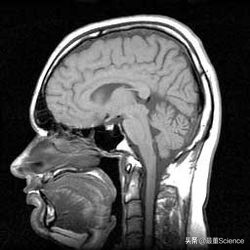

1973年,美国科学家保罗·劳特布尔引进梯度磁场技术,并逐点诱发无线电波,最终获得了世界上第一幅二维的人类大脑核磁共振图像。

人类大脑核磁共振图像